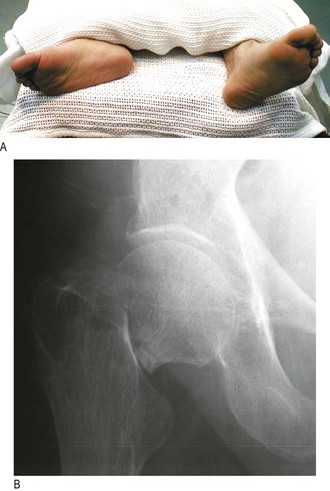

Fracture of the neck of femur is common following relatively minor trauma in postmenopausal women and those over 70 years. The fracture may be minimally displaced or impacted and need not have the classical appearance of a shortened, externally rotated leg (Fig. 14.43A). The patient may even be able to weight-bear.